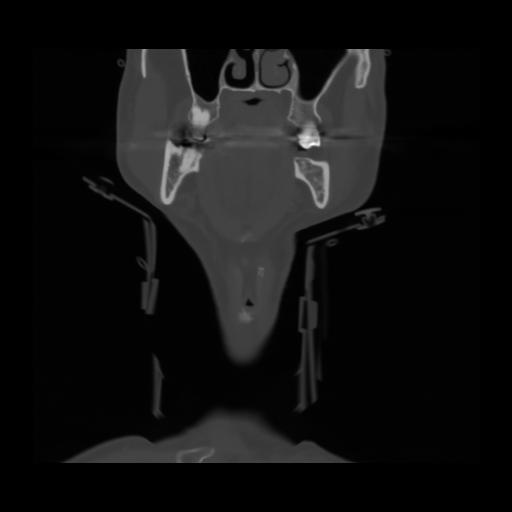

13 P.BLANDAS,,Coronal,2.000,P.BLANDAS,Coronal,